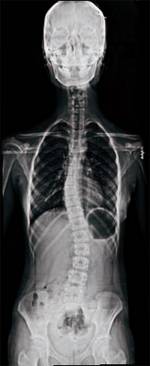

나쁜 자세를 오래 유지하다 보니 척추가 S자 모양으로 휘어 장기를 압박하고 있다. 골반·어깨도 한쪽으로 기울었다. [바른자세협회제공]